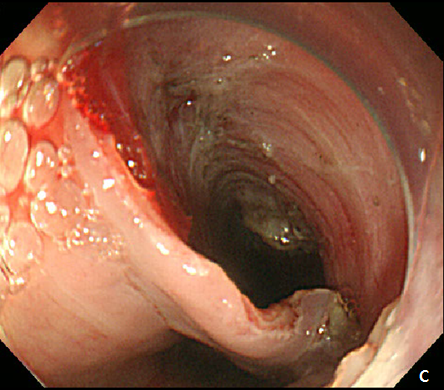

Figure 3 Endoscopic treatment of esophageal stricture.

(A) A follow-up esophagogastroduodenoscopy (EGD) at 1 month after the procedure revealed significant stricture at esophagus. (B) Repeatitive endoscopic balloon dilation was performed. (C) After 8 times of endoscopic ballooning, esophageal stricture was resolved.